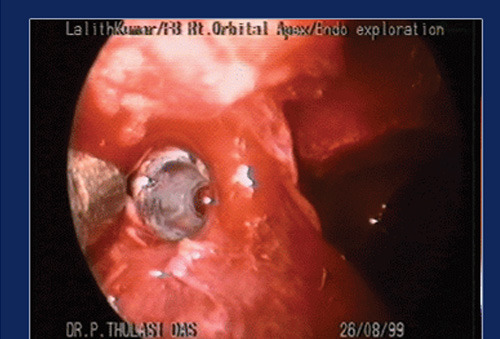

Transnasal Endoscopic approach is employed for removal of tumours and other lesions from the medial and infero medial orbit. The lamina papyracea is a paper thin bone, which can be deliberately opened to expose the orbital contents and extraconal lesions can be removed without much difficulty.

The medial rectus fills almost the entire medial orbit and prevents exposure of the intraconal structures and orbital apex. We have devised a technique of retracting this muscle downwards and posteriorly without compromising its function to obtain good exposure of the Orbital Apex. Well defined, capsulated lesions can be successfully and completely removed using this technique, with little morbidity. We have employed this technique in 30 cases and almost perfected it.

An endoscopic medial orbitotomy and medial retraction techniques were employed to expose the tumour and the same removed in toto